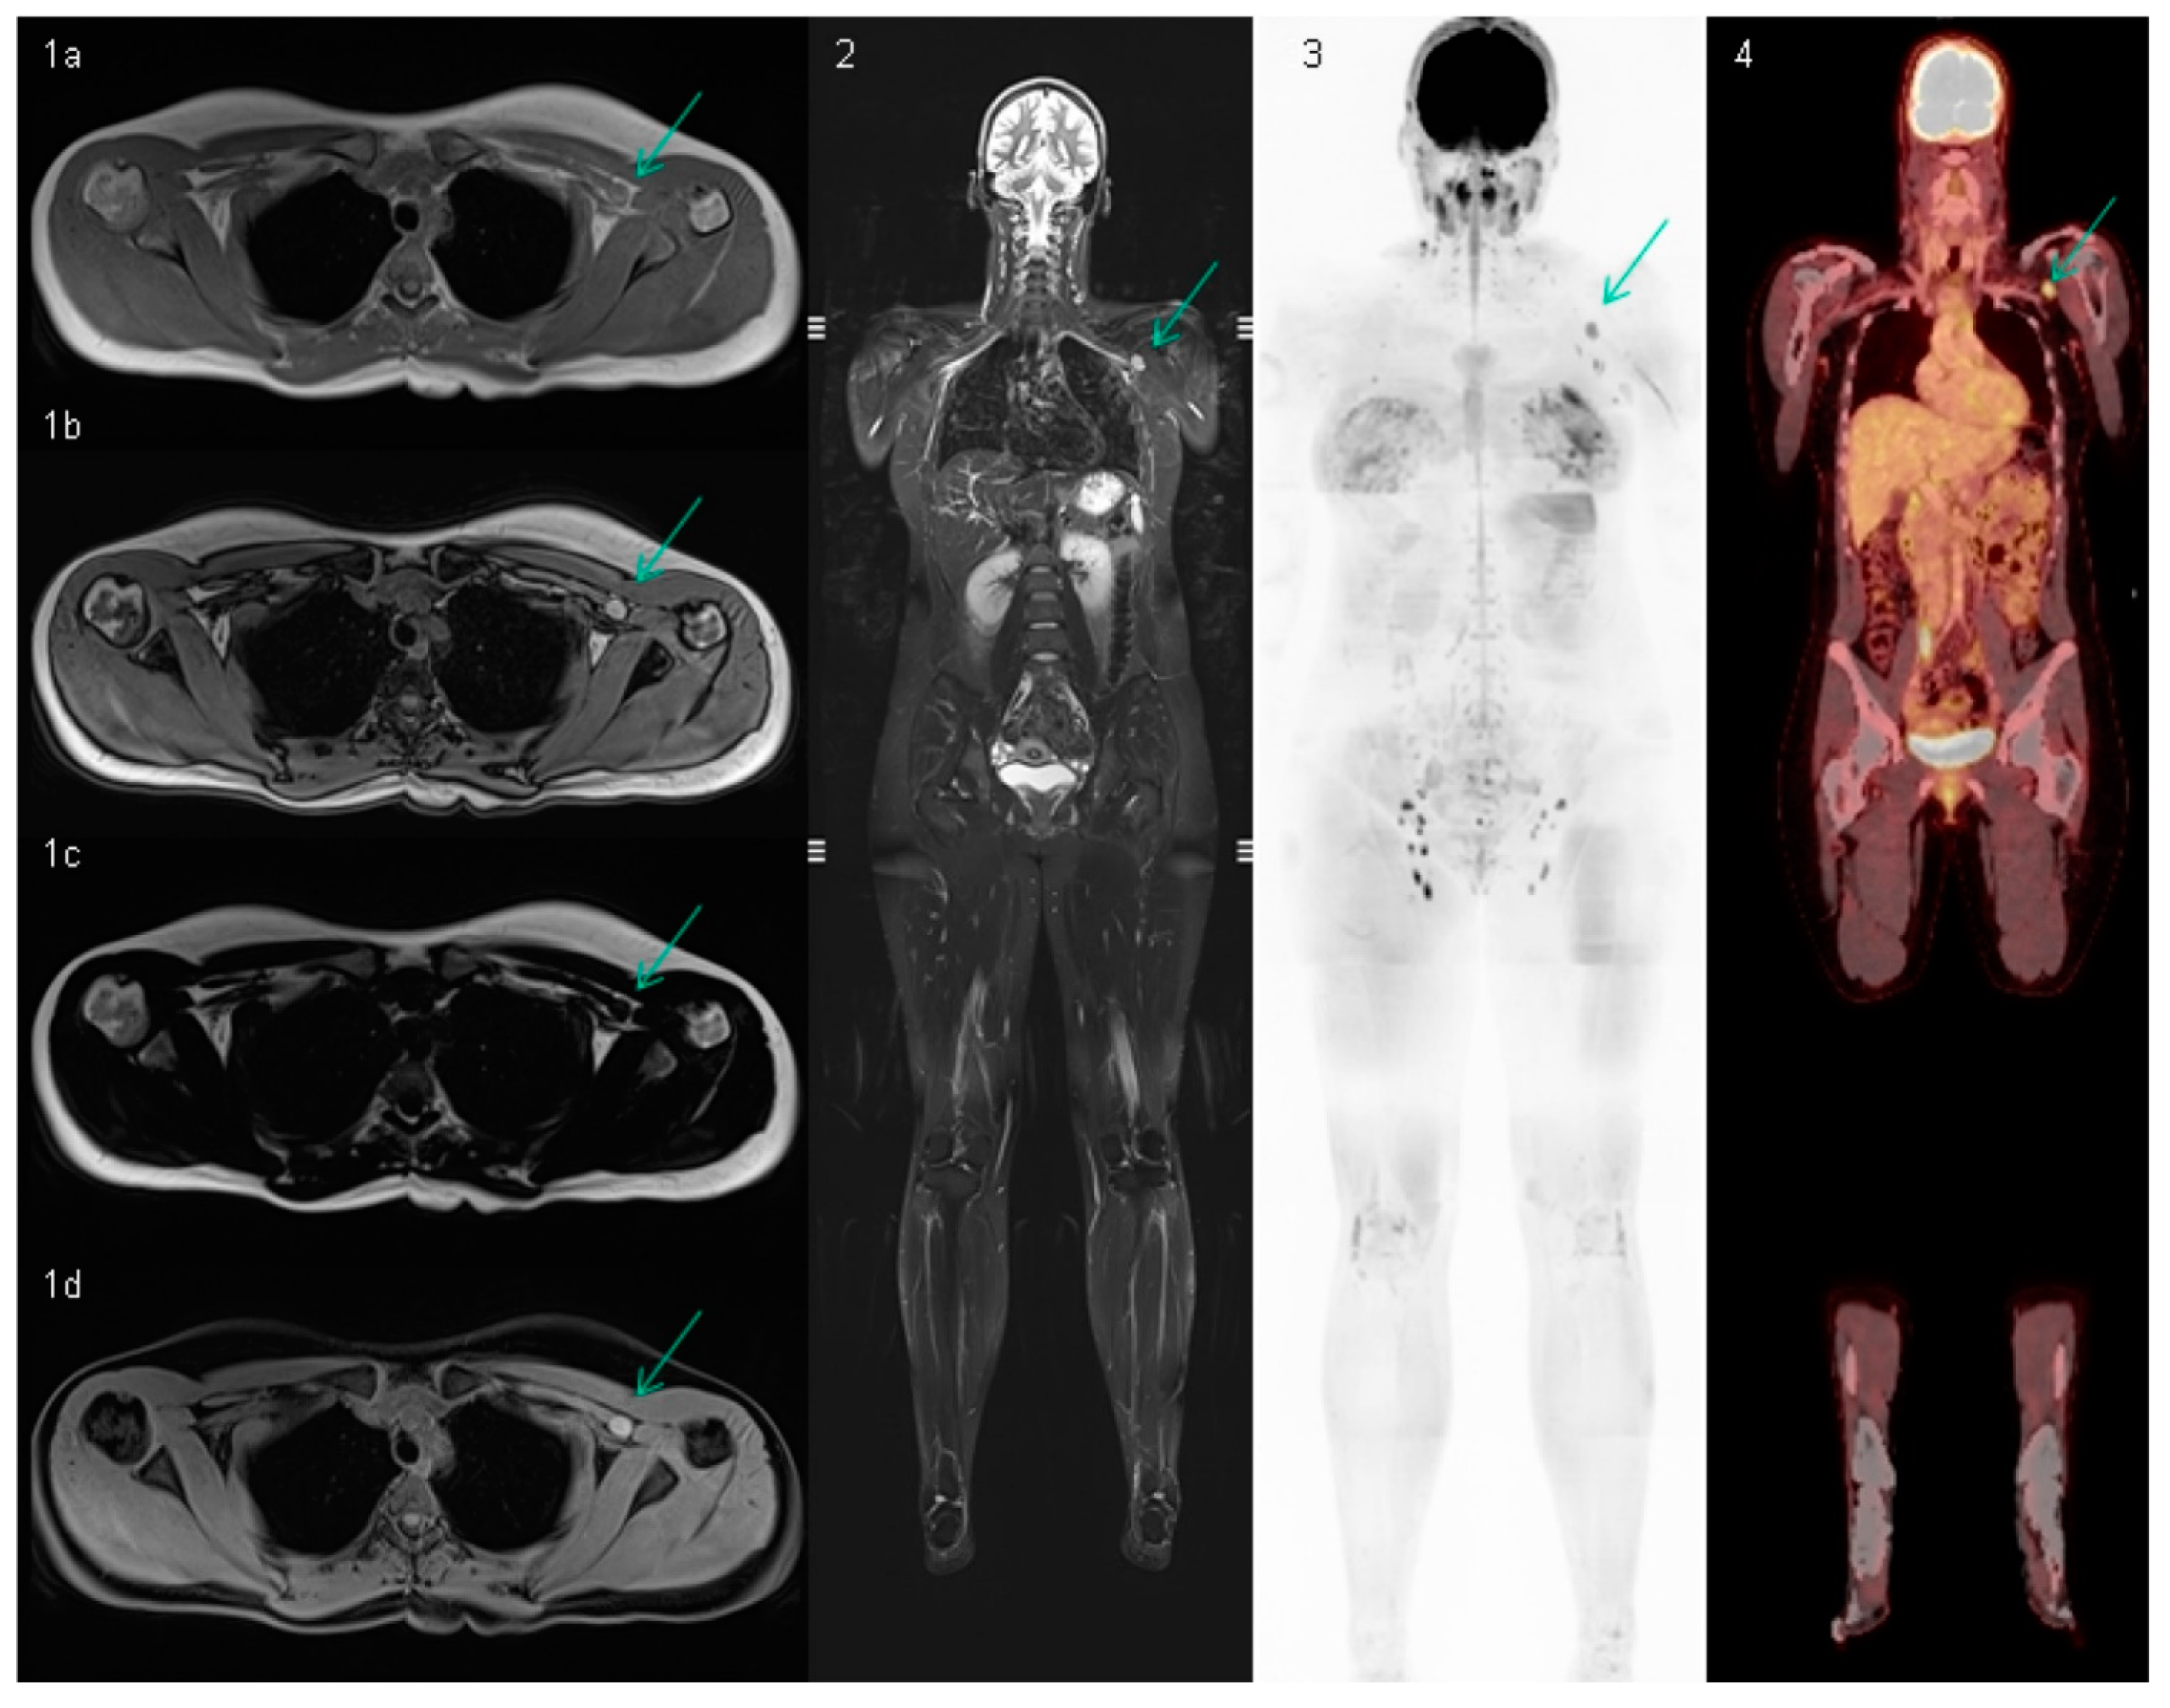

3.3. Whole-Body MRI Performance